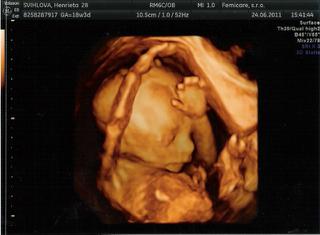

@henrieta44 jejoo, je nádhrená! blahoželám k dievčatku 😀 fakt máme obdobie dievčatiek 😀

@henrieta44 gratulujem k princeznej... 😵

@micicka ĎAKUJEM, ešte stále som z toho taká vzrušená ako malé decko z novej hračky 😀 , zdá sa že aj tento raz ma moja intuícia nezklamala, hlavne nech mi je zdravučká a robí nám obrovskú radosť ( už teraz je tá radosť maximálna) 😉